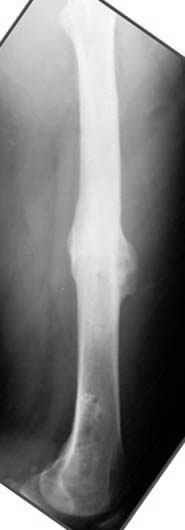

На рисунке N1 предоперационный план лечения ложного сустава шейки бедра- линия ложного сустава, угол и направление введения импланта, клиновидная остеотомия в градусах и миллиметрах, второй снимок после коррекции, расчет, на сколько удлиняется конечность и размеры импланта;

N3 рисунок окончательный снимок, после операции моя рентгенограмма должен выглядеть примерно как эта картина. На N4 снимке клин перед удалением; N5 послеоперации 3 нед.; N6 окончательная рентгенограмма.

варус при проксимальном отделе 95 градусной пластиной.

пластическая модель; и коррекция бедра аппаратом Илизарова.